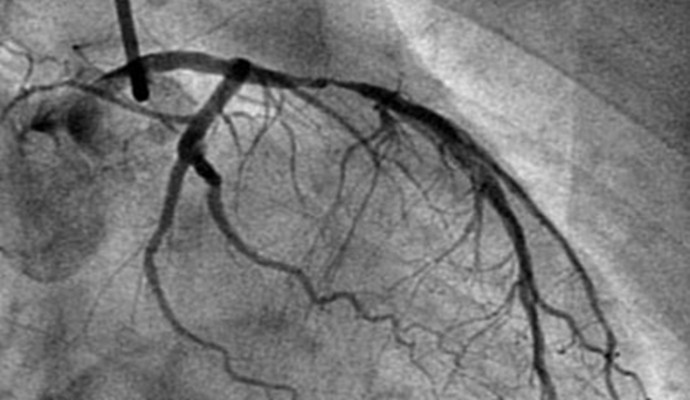

4、冠狀動脈造影

冠狀動脈造影是目前冠心病診斷的“金標准”。可以明確冠狀動脈有無狹窄、狹窄的部位、程度、范圍等,並可據此指導進一步治療所應采取的措施。